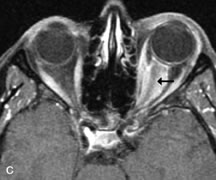

Extraocular muscle enlargement in patients with thyroid-associated orbitopathy is demonstrated equally well with CT and MRI studies. However, the superior tissue contrast on MR images reveals better details of the relationships of the optic nerve to the thickened muscles at the orbital apex (Fig. 16).50 In addition, MRI may be able to differentiate between muscles that are enlarged as a result of edema and active inflammation and those enlarged because of fibrosis by their T2 relaxation times.21 Quantitative MRI was not found to be accurate in predicting the success of low-dose orbital irradiation.51 However, a muscular index relating the diameters of the rectus muscles to the bony orbital dimensions was useful in predicting optic nerve compression.52

Fig. 16. A-C, T1-weighted MR scans obtained with a high-resolution surface coil demonstrate fusiform enlargement of the extraocular muscles. The medial, lateral, and inferior rectus muscles are especially involved. Note the relative sparing of the tendinous insertions, a finding characteristic of this disease process, as well as fatty infiltration of the lateral and inferior rectus muscles. There is marked proptosis, best visualized on the sagittal image (A), and mild crowding of the optic nerve at the orbital apex.